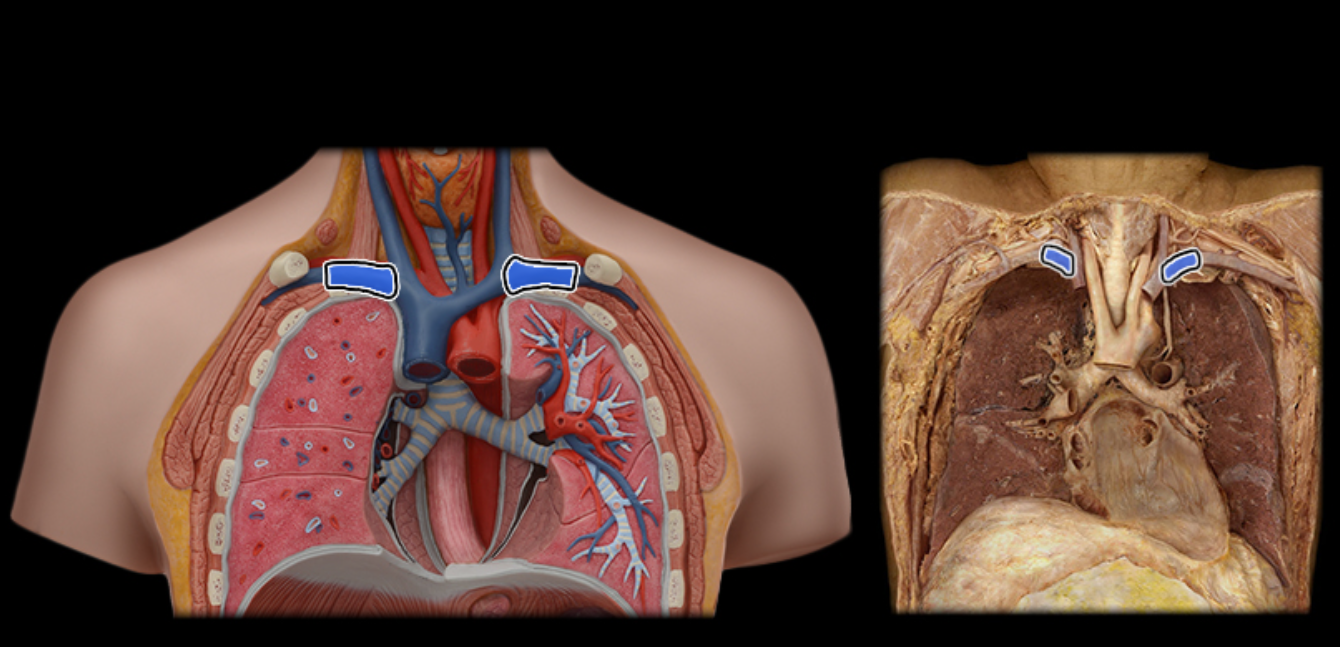

Brachiocephalic v.

Common carotid a.

Internal jugular v.

Pulmonary a.

Pulmonary vv.

Subclavian v.